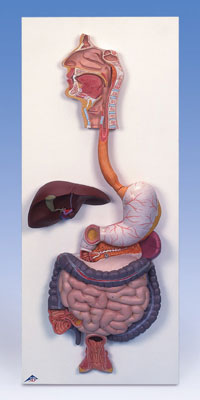

APARATUL DIGESTIV

APARATUL DIGESTIV Aparatul digestiv este constituit din totalitatea organelor care au ca functii principale digestia si absorbtia principiilor alimentari si eliminarea reziduurilor neasimilabile ale alimentelor ingerCiteste tot ... 1835 cuvinte